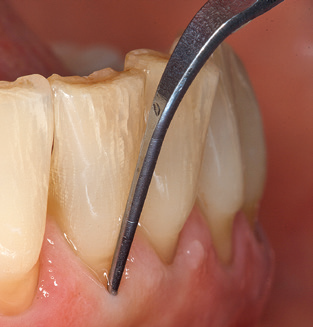

Una buona illuminazione del campo di lavoro facilita notevolmente il processo. Il sistema utilizzato dagli autori ottiene questo risultato grazie a un anello LED 5x integrato nel manipolo. Naturalmente, viene offerta anche una serie di consigli di lavoro per diverse indicazioni. Un inserto diritto, utilizzabile universalmente, è lo strumento di base necessario per la pulizia meccanica dei denti naturali (Fig. 5a e b). Sono disponibili anche inserti curvi, che consentono l'accesso alle forcazioni esposte, per le aree difficili da raggiungere nella regione posteriore (Fig. 6).

Fig. 4: Sonde flessibili con marcature millimetriche sono consigliate per il sondaggio di impianti dentali (ad es. Colorvue Kit PCV11KIT6, HuFriedy). - Fig. 5a e b: Un inserto diritto (1P, W&H Dentalwerk Bürmoos GmbH) è uno strumento adatto per l'uso su tutti i denti naturali. - Fig. 6: Inserti curvi (3Pr / 3Pl, W&H Dentalwerk Bürmoos GmbH) si prestano alla lavorazione di aree difficili da raggiungere del dente e delle superfici radicolari (ad es. Forcazioni). - Fig. 7: L'inserto esagonale conico per la pulizia dell'impianto (1I, W&H Dentalwerk Bürmoos GmbH) consente una pulizia atraumatica ed efficace della superficie della corona e del moncone. - Fig. 8: Le curette in titanio e carbonio sono strumenti adatti per la pulizia manuale delle superfici dell'impianto.